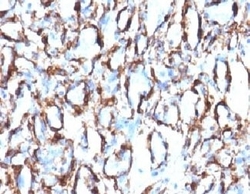

- Formalin-fixed, paraffin-embedded human angiosarcoma stained with alpha Smooth Muscle Actin antibody (ACTA2/791). This image was taken for the unmodified form of this product. Other forms have not been tested.

- Formalin-fixed, paraffin-embedded human angiosarcoma stained with alpha Smooth Muscle Actin antibody (ACTA2/791). This image was taken for the unmodified form of this product. Other forms have not been tested.

- Formalin-fixed, paraffin-embedded human angiosarcoma stained with alpha Smooth Muscle Actin antibody (ACTA2/791). This image was taken for the unmodified form of this product. Other forms have not been tested.